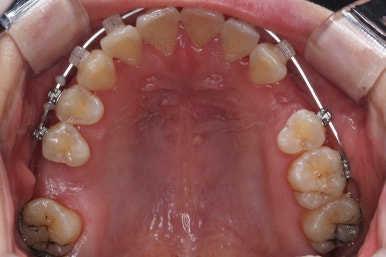

1. 초진

초진 시 입안의 모습입니다.

당장 눈에 띄는 부분은 아래 앞니 사이에 틈새가 있어 치석도 많이 쌓여있는 상황이고요.

윗니-아랫니를 각각 보면 치아가 썩고 부러져 뿌리만 남은 치아가 많이 보입니다.

남은 치아들도 곳곳에 충치가 보이고요.

또 전반적으로 앞니가 앞으로 밀려나와 뻐드러져 있는 모습도 관찰되네요.